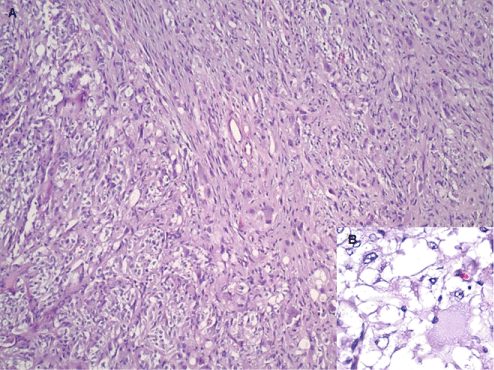

Figure 3: Hematoxylin and Eosin stain showing all three elements of gangliocytic paraganglioma - nests of epithelioid cells forming a Zellballen pattern, fascicles of spindled sustentacular cells, and scattered large ganglion cells (A - 20X original magnification). The insert (B) shows epithelioid cells and ganglion cells with eccentric nuclei and abundant eosinophilic cytoplasm. (40X original magnification). View Figure 3